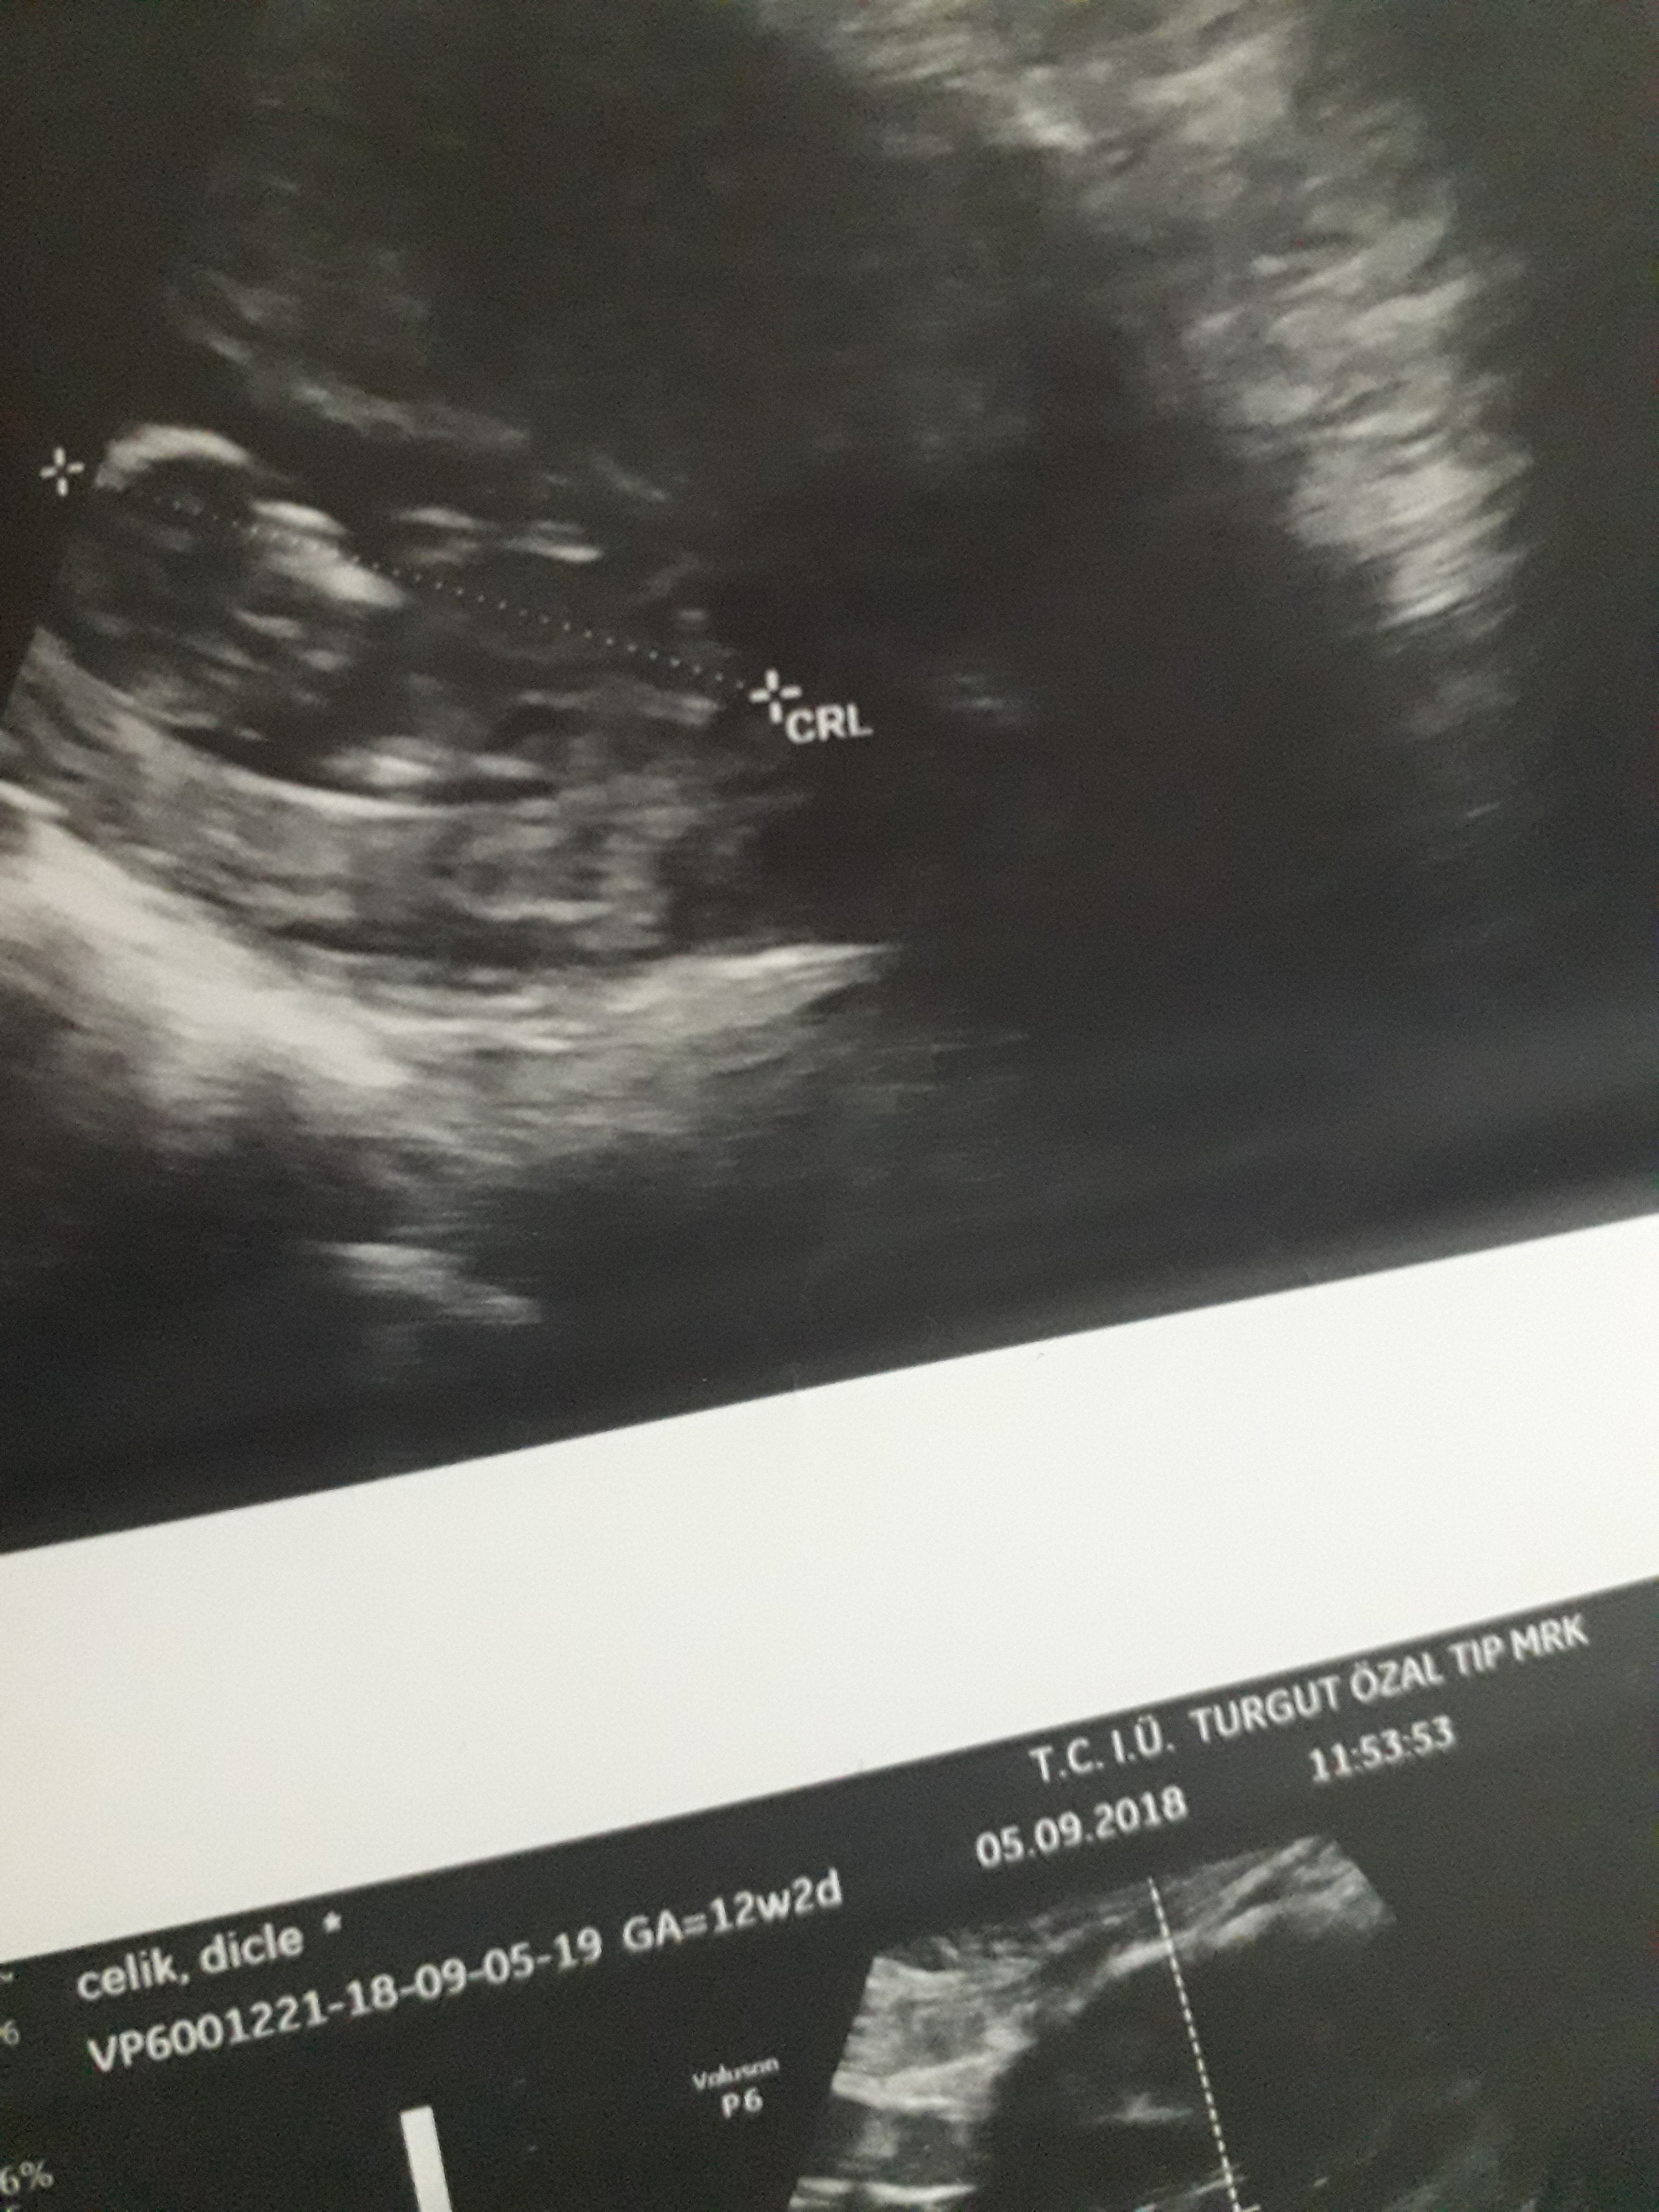

Dun malatyada verildi 12 +4 gunluk lutfen yorumlayin

nub çıkıntısının üzerinde imleç var cinsiyet anlaşılmıyor ilk sayfayı incelemenizi öneriyorum görselin kalitesi konu içinde yer alan görselle aynı olmalıdır.

Görsellerde nub çıkıntısı belli değil . Ultrasonu yapan doktor cinsiyeti hakkında bilgi vermiştir mutlaka ama şunu belirtmeden geçmeyeyim. Bu haftalarda cinsiyet tahmininde yanılma payı çok yüksek 17-19 ve 20 ci haftalarda bebeğin cinsiyetini net olarak öğrenebilirsiniz.